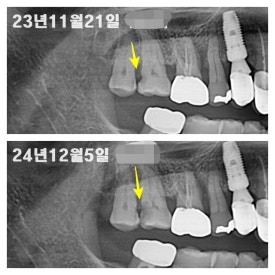

3. 충치치료 안 하시다가 결국 발치를 해야 했던 케이스

충치가 그나마 덜 진행되었을 때는 신경치료 후 크라운 치료를 통해 해결할 수 있었는데 치료를 미루다가 결국 충치가 더욱 광범위해진 상태로 오셔서 발치를 하게 되었던 케이스입니다.